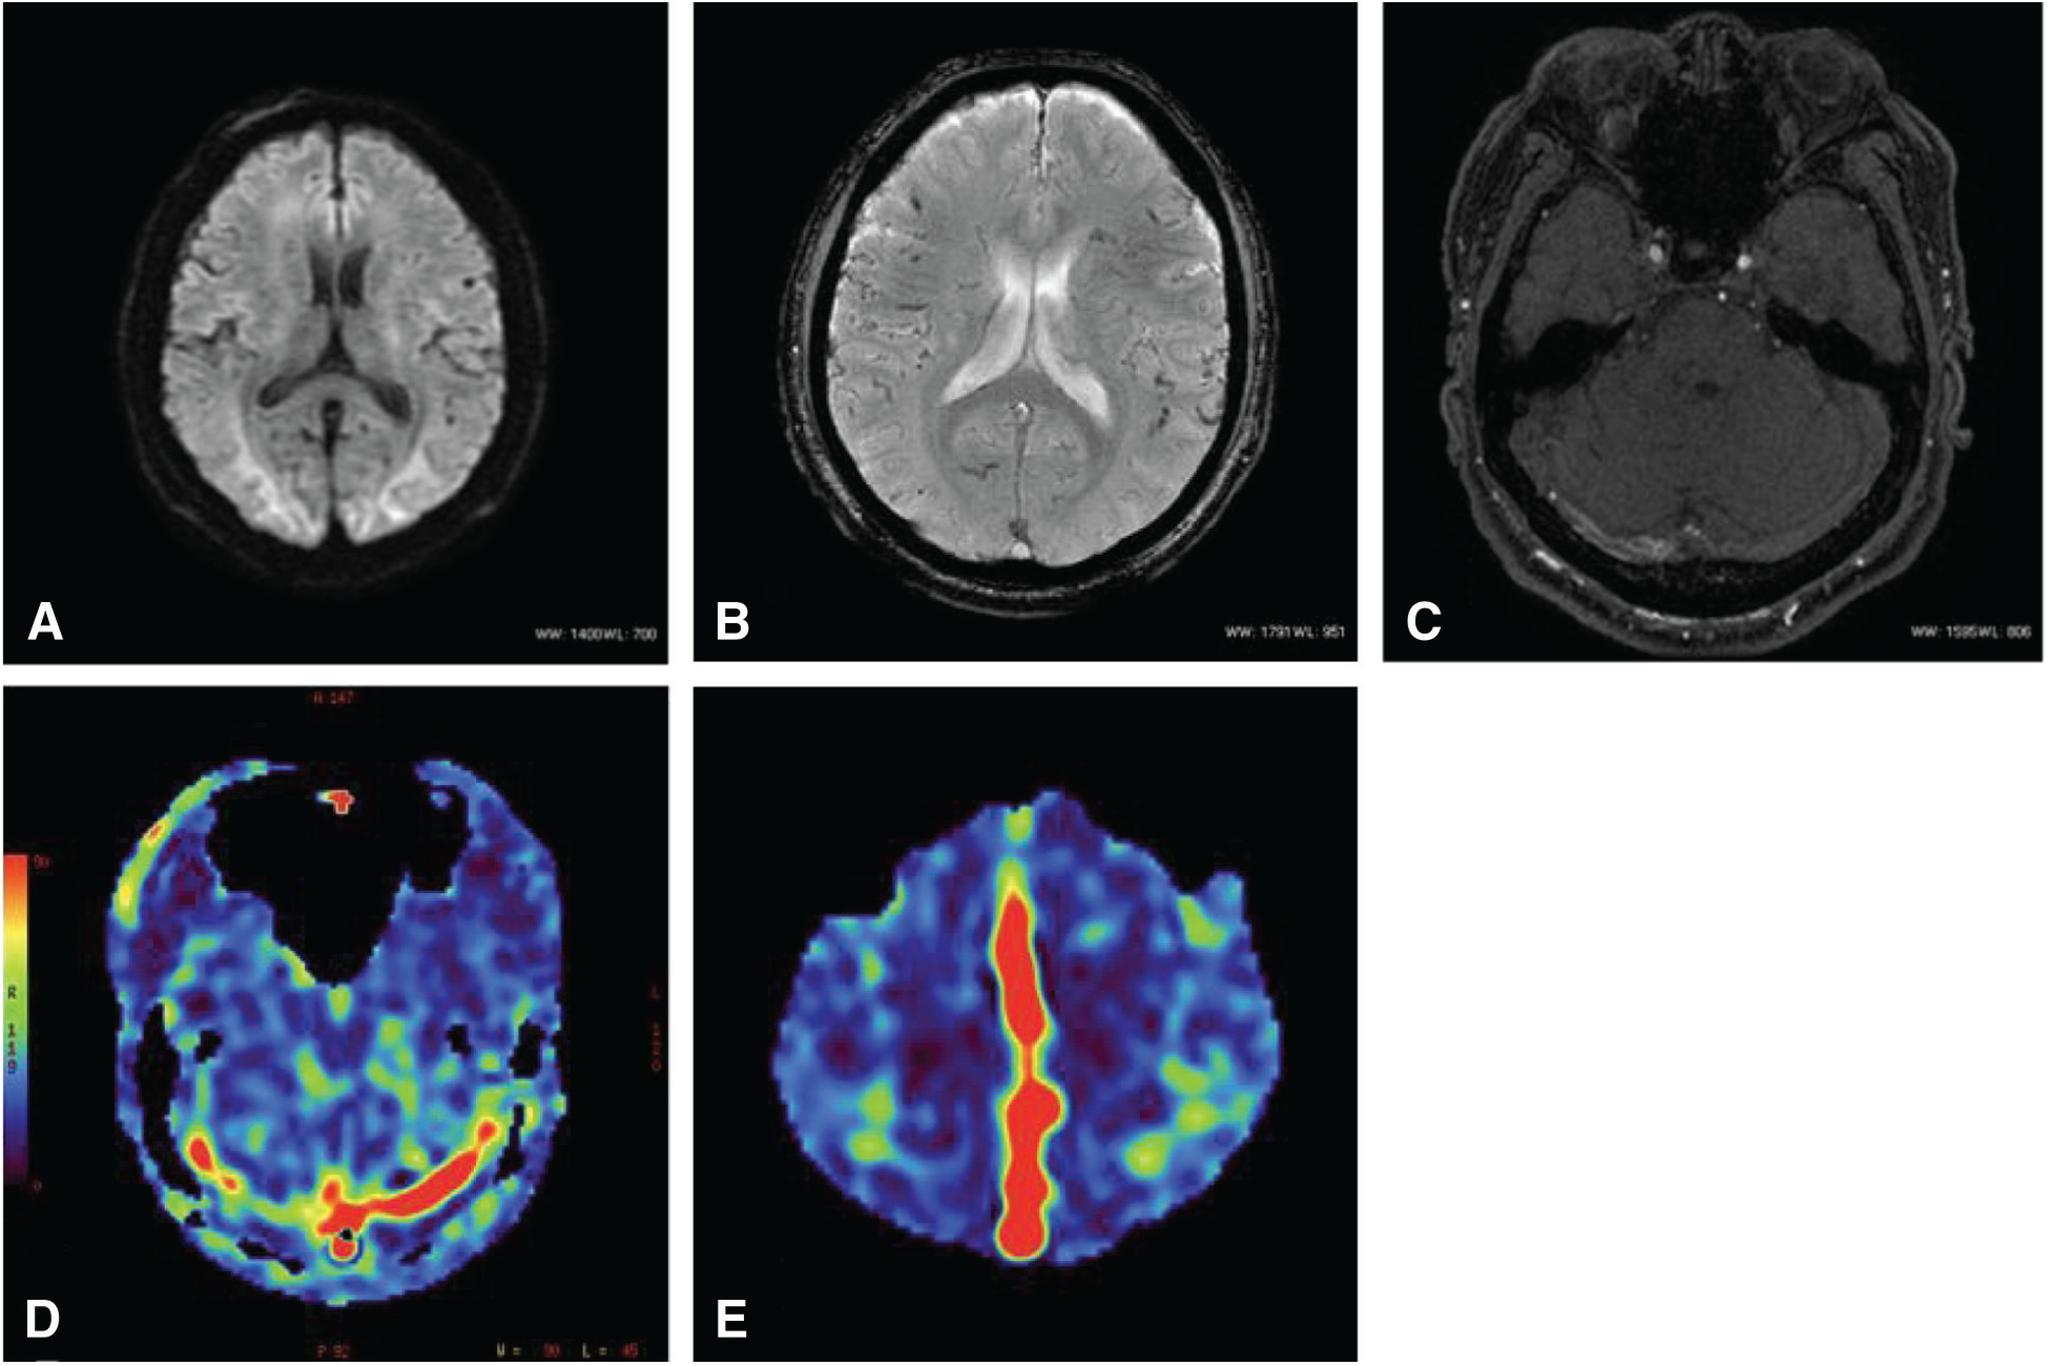

The patient was a 65-year-old man. Cerebral angiography demonstrated an aggressive dAVF involving the TSS, superior sagittal sinus (SSS), and the sinus confluence, with severe cortical and deep venous reflux. We performed multiple transarterial and transvenous embolizations for the TSS and sinus confluence lesion. The shunt disappeared almost completely after embolization. A high signal intensity that had been apparent in the SSS and straight sinus (StS) on ASL imaging before embolization disappeared after embolization. ASL imaging 3 months after embolization revealed slightly a high signal intensity in the StS, which was considered to be due to recurrence of the lesion. Moreover, recurrence of the confluence and TSS-dAVF was observed on cerebral angiography 6 months after embolization. As additional embolization was considered difficult, radiation therapy was recommended, but the patient refused; therefore, follow-up was performed. As ASL imaging findings were consistent with cerebral angiography findings, careful examination and monitoring of changes on ASL imaging were subsequently performed.

患者为一名65岁男性。脑血管造影显示为侵袭性硬脑膜动静脉瘘,累及横窦、上矢状窦(SSS)和窦汇,伴有严重的皮质和深部静脉逆流。我们对横窦和窦汇病变进行了多次经动脉和经静脉栓塞治疗。栓塞后分流几乎完全消失。栓塞前ASL成像中在SSS和直窦(StS)中明显的高信号强度在栓塞后消失。栓塞后3个月的ASL成像显示StS中有轻微的高信号强度,这被认为是由于病变复发所致。此外,栓塞后6个月的脑血管造影显示窦汇和TSS-dAVF复发。由于考虑再次栓塞困难,建议进行放射治疗,但患者拒绝;因此,进行了随访。由于ASL成像结果与脑血管造影结果一致,随后对ASL成像的变化进行了仔细检查和监测。